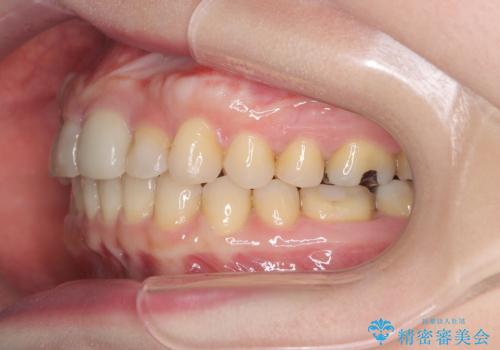

- 「八重歯をきれいにしたい」とのご希望で来院されました。診察の結果、上顎犬歯の萌出スペースが不足しており、典型的な八重歯(叢生)の状態でした。上下の歯の中心(正中)のずれや、奥歯のかみ合わせ(臼歯関係)のアンバランスも見られたため、単に見た目を整えるだけでなく、全体的な機能改善も必要と診断しました。

初期段階では、リンガルアーチを上顎に装着し、奥歯を少しずつ後方へ移動させていきました。これにより前歯部の歯列に十分なスペースを確保。その後、マルチブラケット(ワイヤー矯正)を用いて、突出した八重歯を正しい位置に誘導しながら、歯並び全体を整えていきました。

治療中は咬合バランスや歯列の中心(正中)の位置にも注意を払い、最終的には上下の正中が一致し、左右の臼歯関係も理想的な形に改善されました。見た目の変化はもちろん、かみ合わせの安定や清掃のしやすさも向上。